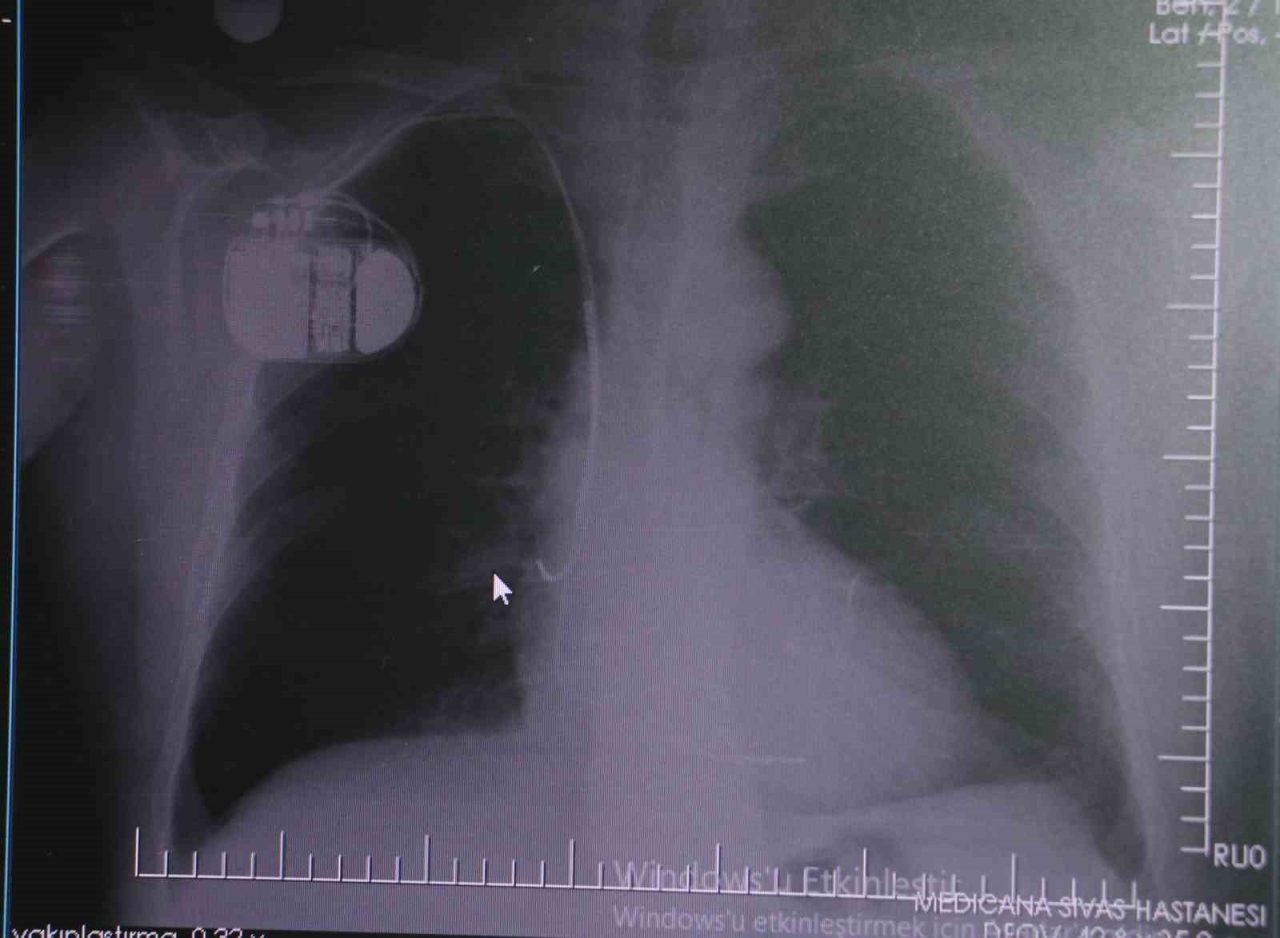

Kalp pilleri ile MR cihazına girilebileceğini belirten Erdoğu, “Çok büyük bir ameliyat değil ama yine de ciddi bir cerrahi işlem. Kalp pili, tıpta son 30 yılda yaşanan gelişmelerden en büyüğü. Bir bilgisayarın küçültülüp insan vücuduna konulmuş hali aslında. İnsan ömrünü ciddi oranda uzatan bir tedavi. İnsanlar bir şokla hayata tutunurken, pil olmasaydı öleceğini düşündüğümüz birçok hastamız var. Kalp pilinin bu özelliği, uygun hastalarda ciddi oranda ani ölümü engelliyor. Hastanın başına gelecek bir kalp durması durumunda yanında bir sağlıkçı yoksa, onun ritmini düzeltecek defibrilatör cihazı yoksa hastayı hayatta tutmak mümkün değil. Uygun endikasyonlarda kalp pili olduğu zaman, pil hastaların ritmini algılıyor ve acilde yapılan şoklamayı yaparak hastayı hayata döndürüyor. Kalp pillerinde yeni teknolojilerle MR’a girmek mümkün, tomografiye zaten girebiliyorlar. Tarama cihazlarından geçmelerini uygun görmüyoruz. Bu tarz durumlarda hastalarımız ’kalp pilim var’ dediğinde muaf tutuluyorlar. Kalp pilleri ciddi teknolojik cihazlardır. Vücudun içindeki titreşimi, örneğin mikser kullanmak, kolunu sallayacak herhangi bir eylem kalp pilinde olumsuz etki oluşturabilir. Soğuk havalarda vücutta oluşan ciddi titremeler kalp pilinin hafızasını karıştırıp kalbin durduğunu düşündürebilir ve gereksiz şoklama yapabilir. Bu tarz kişilerin soğuk havalarda daha temkinli olması gerekir” diye konuştu.